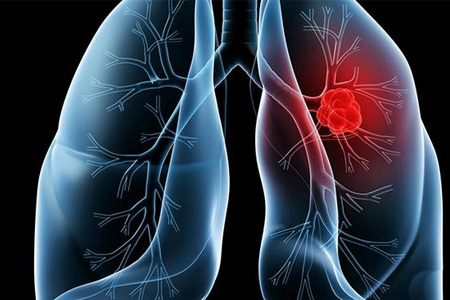

肺部有腫瘤怎麽辦?應對肺部腫瘤:早期發現、綜合治療爲關鍵

肺部腫瘤是一種常見的肺部疾病,對患者的身體健康和生活質量都有嚴重影響。當發現肺部有腫瘤存在時,及早采取有效的治療措施至關重要。以下是一些應對肺部腫瘤的方法和建議。